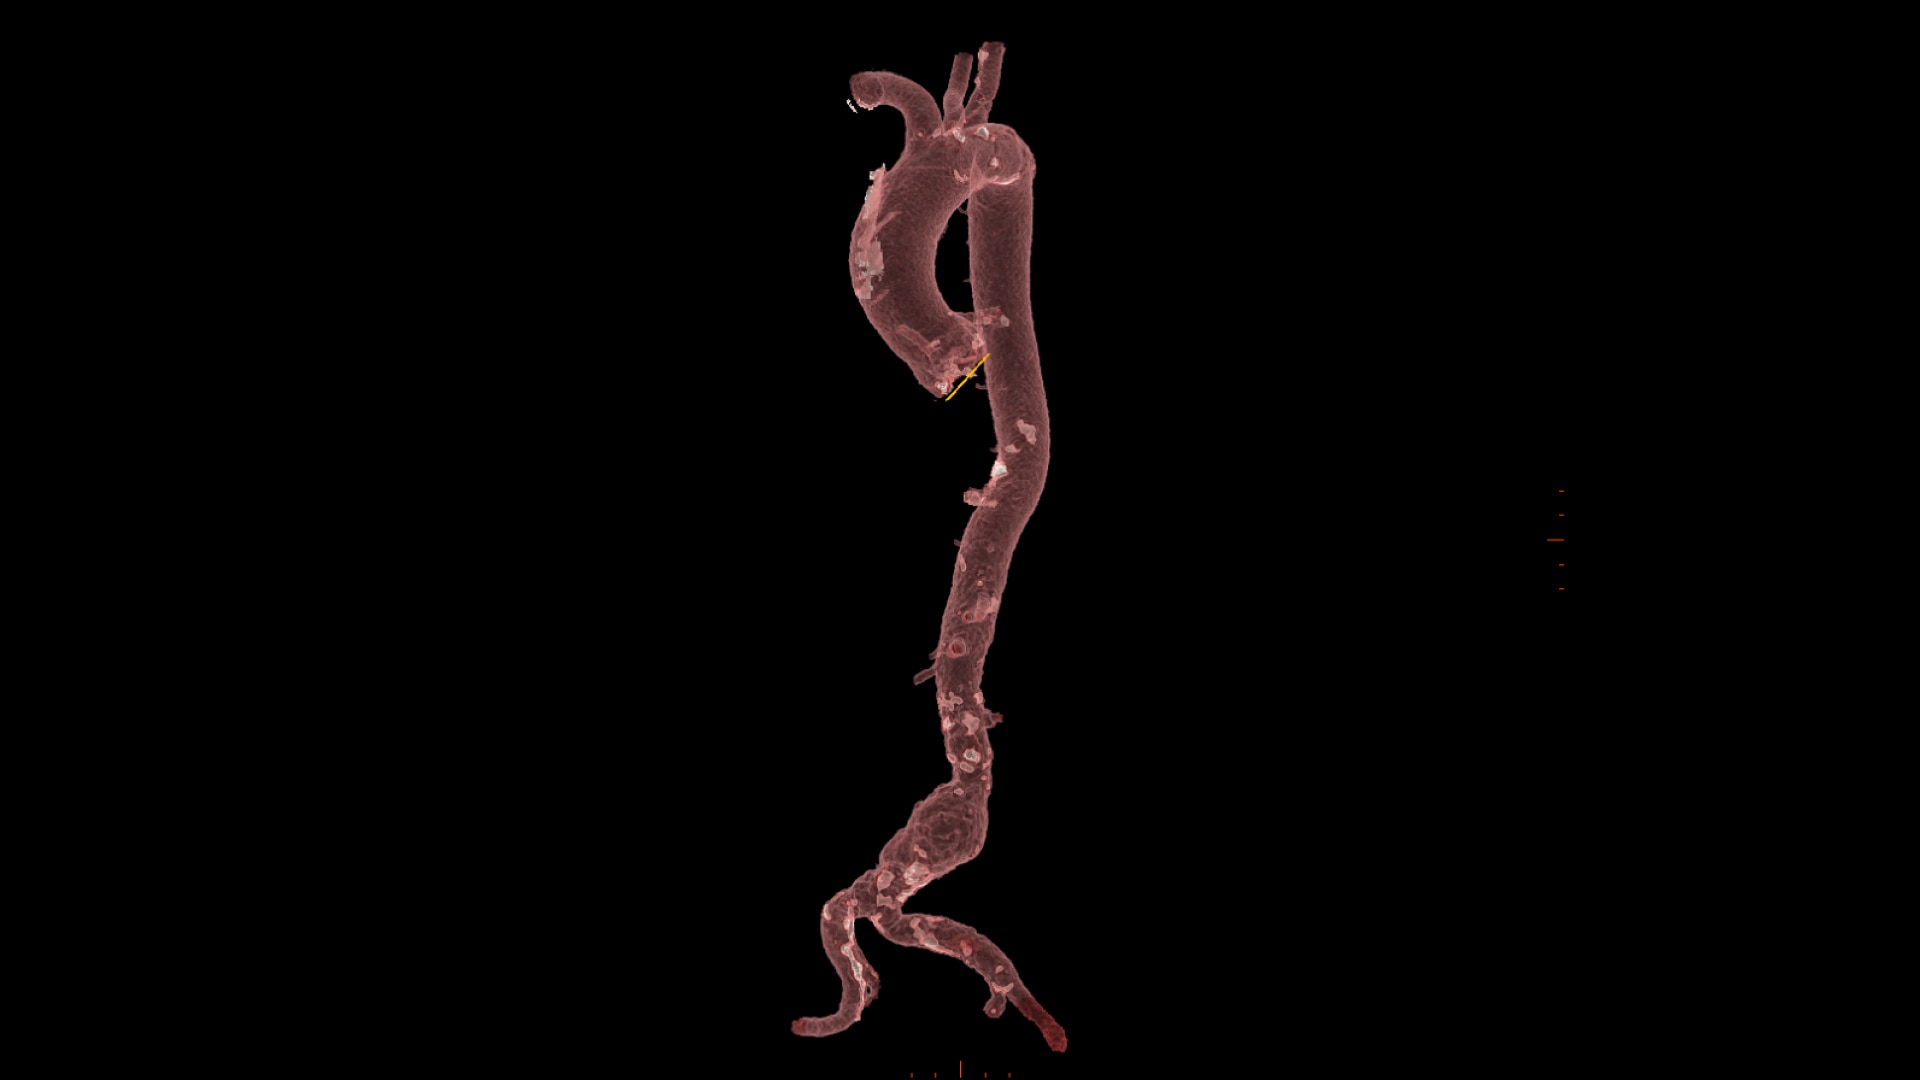

Transcatheter Aortic Valve Implantation

Streamlined workflow for your TAVI procedures

PLAN

0-click aorta segmentation and valve definition makes accurate valve sizing accessible to anyone.